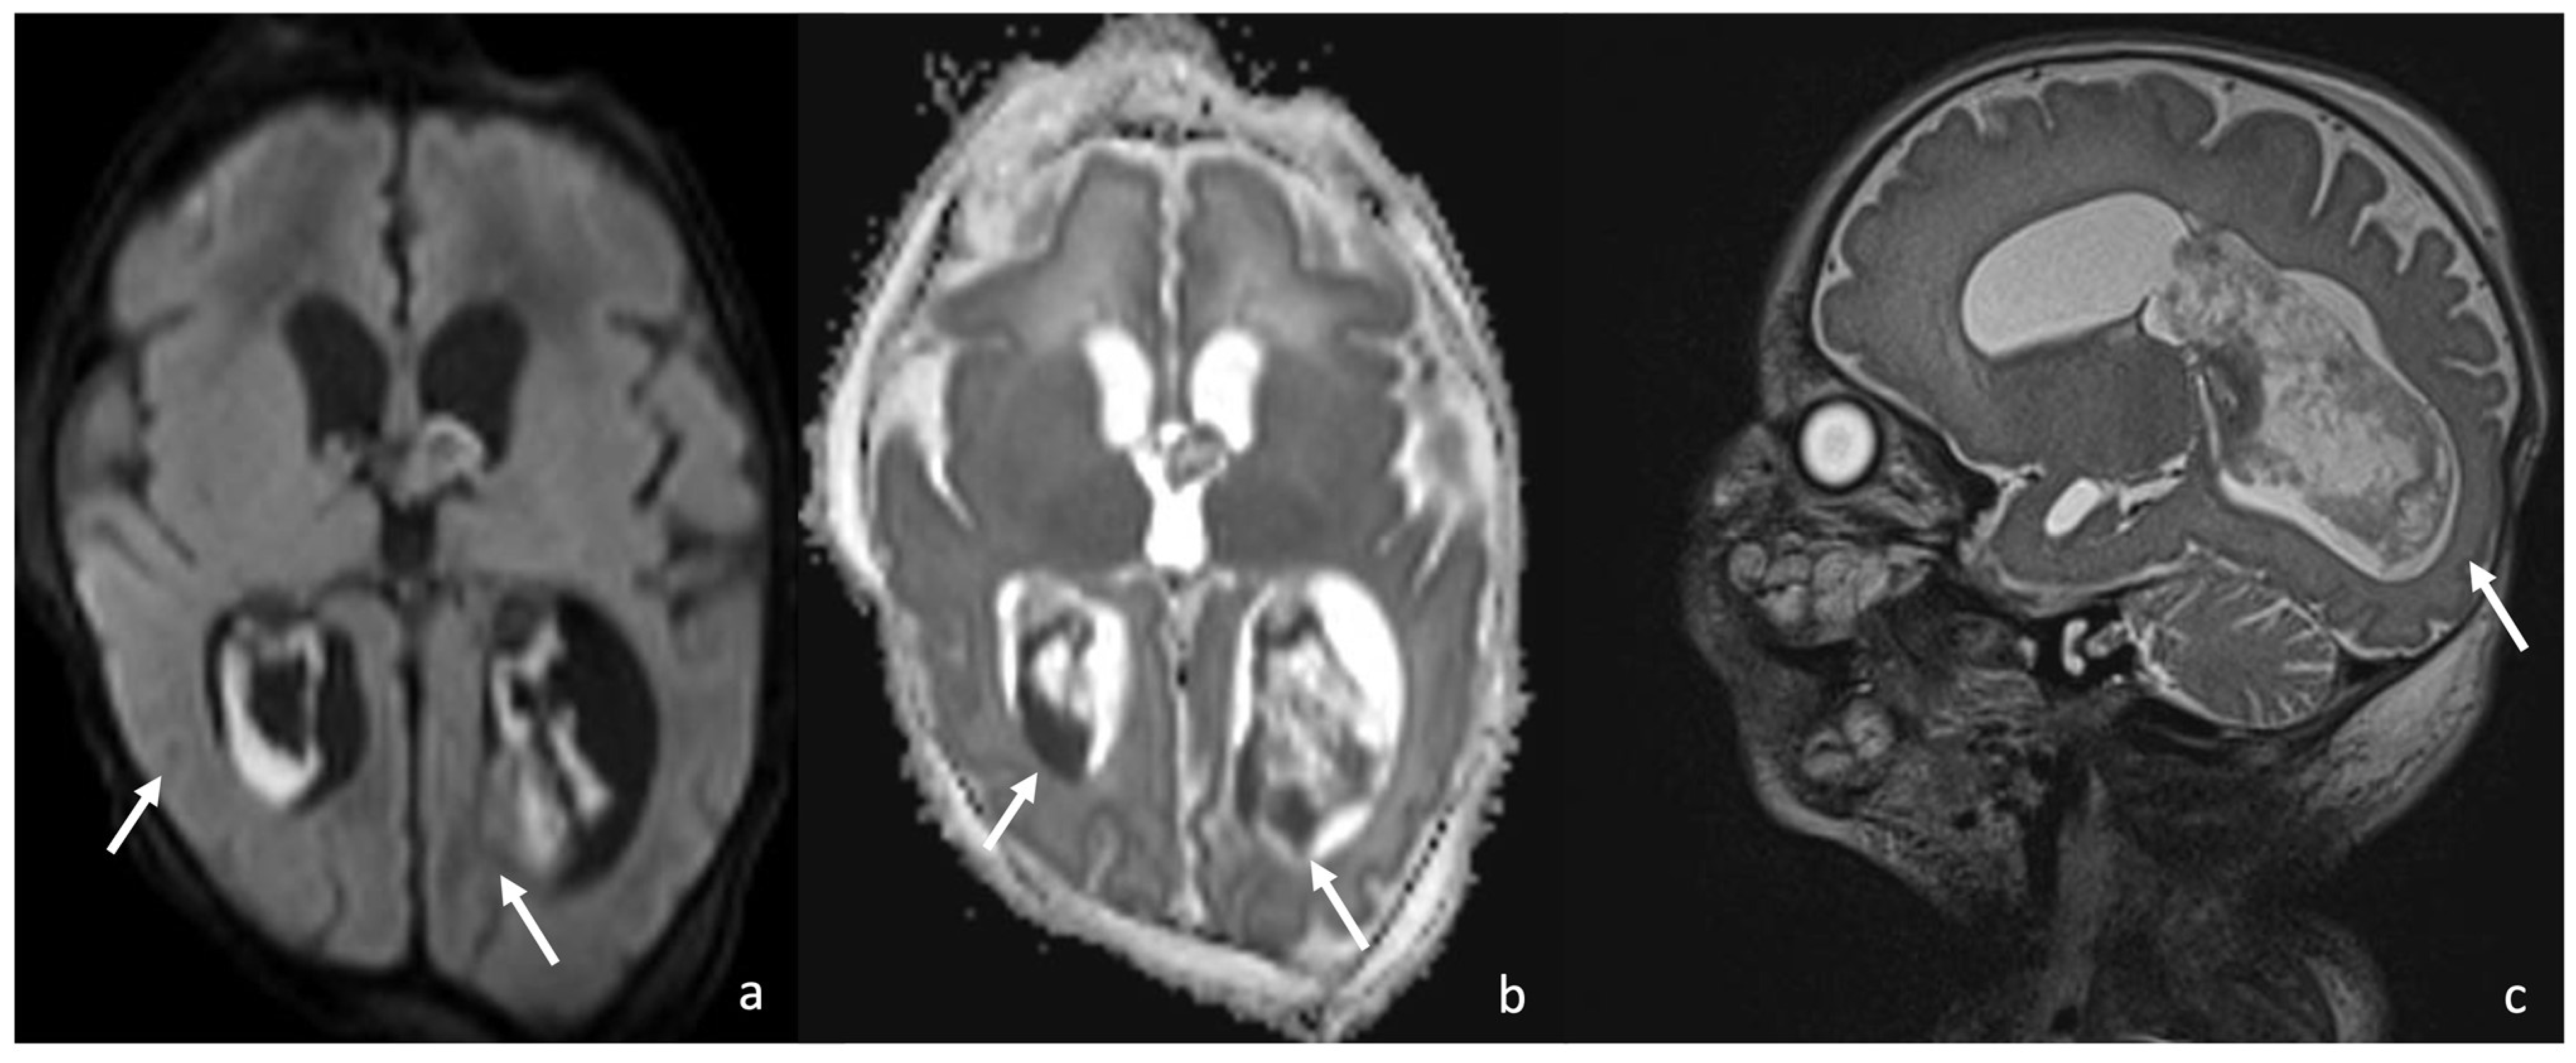

Figure 9.

Two cases of newborns, namely a 1-month-old girl and (e–h) a 2-month-old girl, affected by Group B Streptoccoccus meningoencephalitis (a–d). In both cases, there are multiple punctate ischemic lesions with a massive brain involvement characterized by diffusion restriction on axial DWI sequences (arrows in (a,b,e,f)) and low ADC values (arrowheads in (c,d,g,h)).